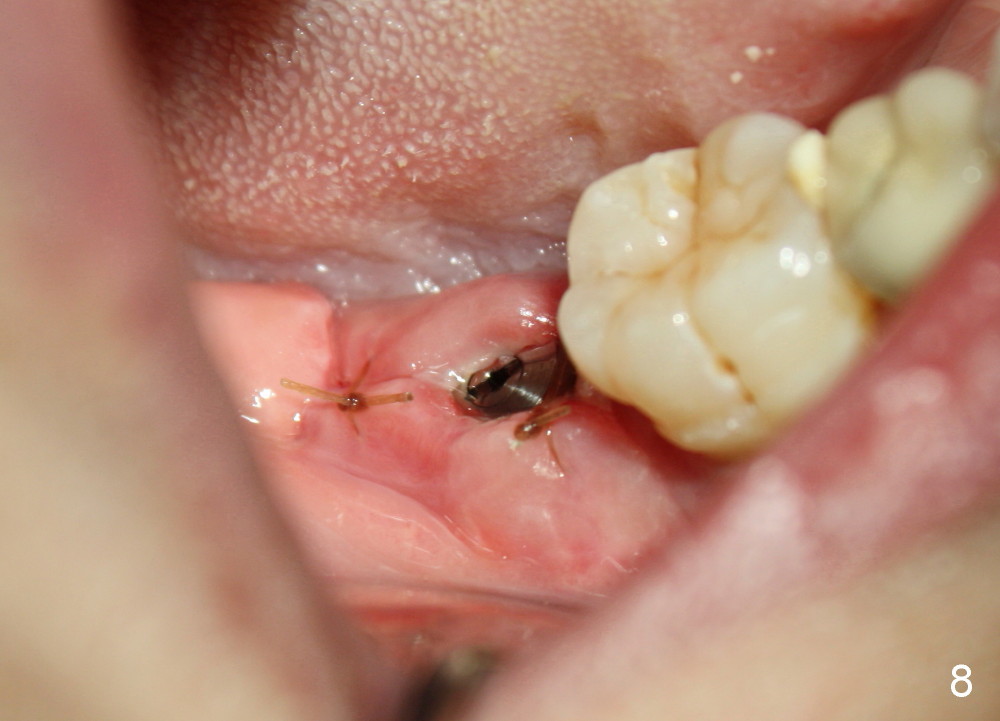

Infiltration anesthesia is administered with 68 mg of Septocaine, 34 mg of Lidocaine, 34 mcg of Epinephrine around the site of the lower right 2nd molar. An incision is made. A 2 mm pilot drill is used to initiate osteotomy at the depth of 8 mm. A parallel pin is inserted for the 1st intraop PA (Fig.4: P), which shows once more time the likelihood of incooperation from the patient. Combined with the information from CT, it appears alright to continue increasing osteotomy in the diameter and depth until 5x11 mm (Fig.5,6 (T: tap)). A 6x14 mm tap is inserted at 11 mm in bone. When the tap is removed, an explorer is used to check the intrigity of the osteotomy walls. No vibration is palpated linguoapically during drilling and inserting taps. There is no abnormal hemorrhage from the osteotomy. Finally 6x14 mm implant is placed as expected (Fig.7). The wound is healing 6 days postop (Fig.8).